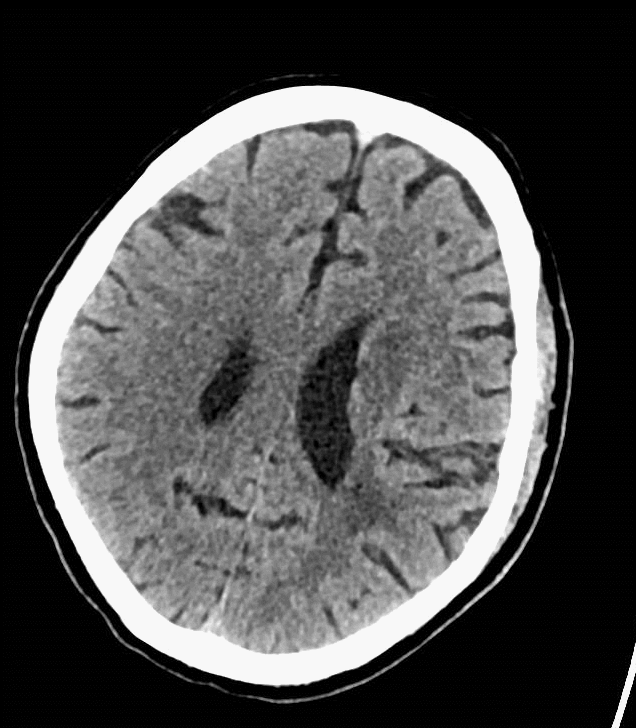

术后复查:颅脑CT平扫未见明显新增脑梗塞。